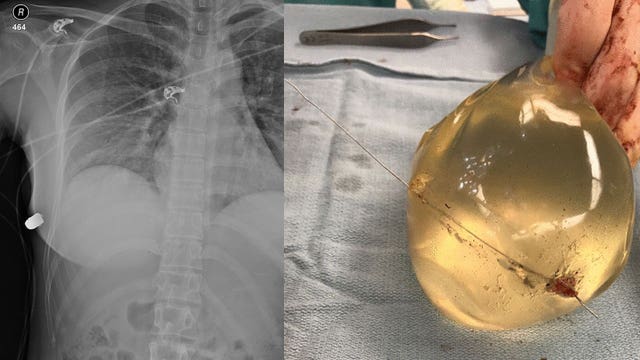

Woman's breast implants believed to save her life from bullet

A woman with breast implants survived a gunshot wound when the silicone insert deflected the 40 caliber bullet, doctors say.